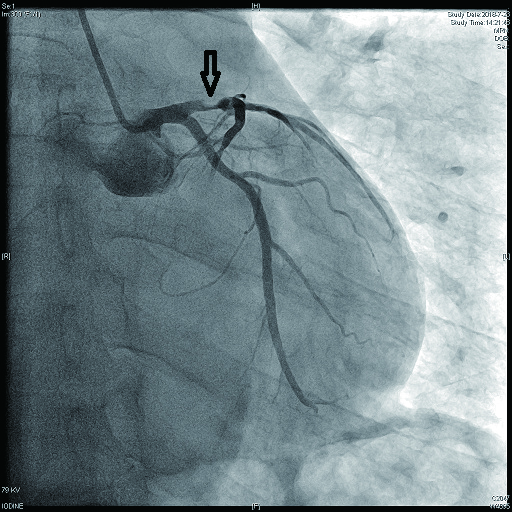

病例2 3(图 6~8 LAD近段 次全闭塞 2级 LAD近段植入支架1枚

图 6 病例2冠脉造影示LAD中段病变

图 7 病例2冠脉造影示LCX病变

图 8 病例2冠脉造影示RCA病变